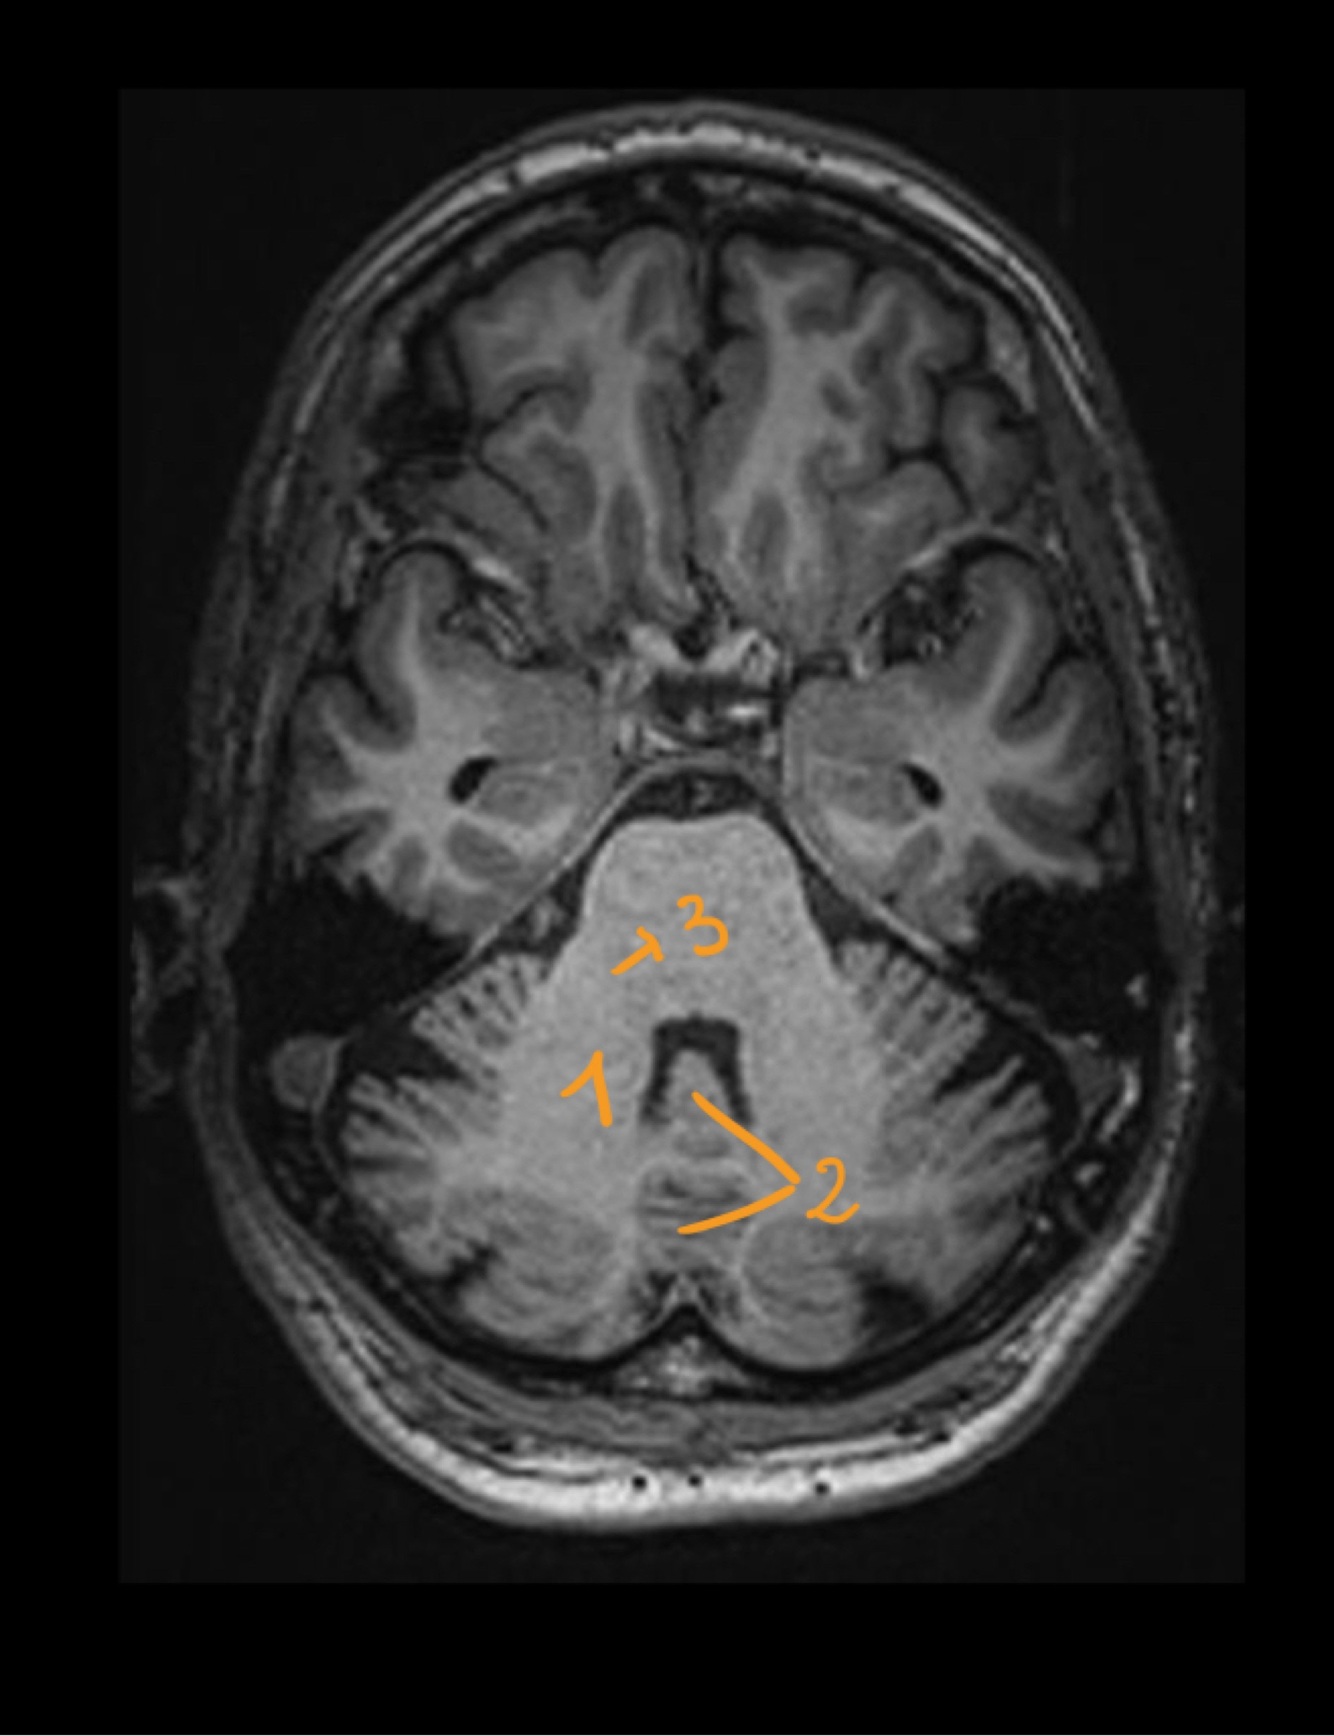

Name the structure

Hypophisis

29

30

4th ventricle